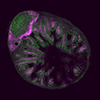

- Flow cytometry, CyTEK, Immunofluorescence microscopy